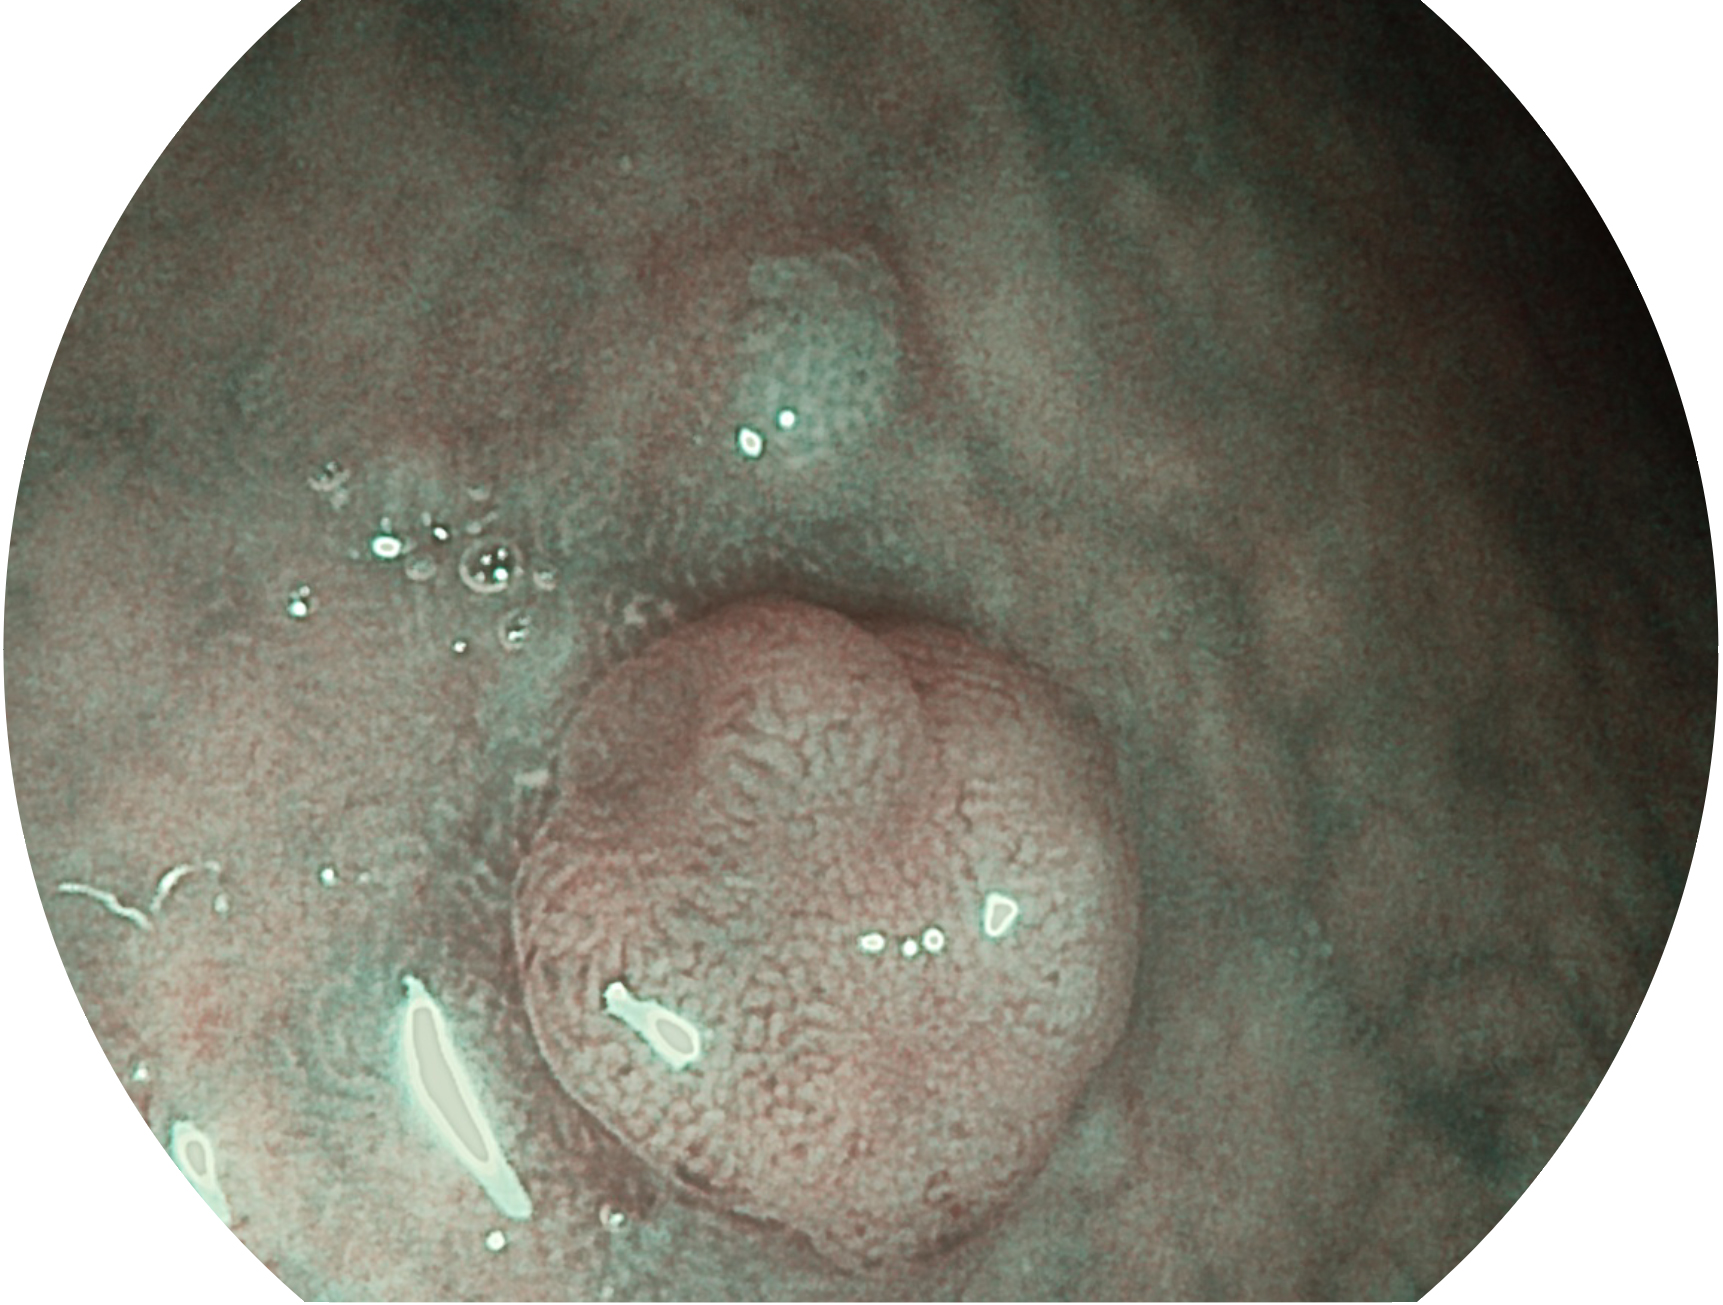

16877太阳集团新开发的内镜染色技术,主要是基于多波长LED 光源的开发,VLS-55Q 四波长LED 光源是由四个不同颜色的LED光按照相应照明模式所规定的特定发光比例进行合束后形成,合束后形成的照明光的光谱由红光、绿光、蓝光及蓝紫光这四个不同的波段范围构成。具有更高光谱自由度,通过光谱比例的控制,实现了聚谱成像技术,英文全称为“Spectral Focused Imaging, SFI”,缩写为“SFI”和光电复合染色成像技术,英文全称为“Versatile Intelligent Staining Technology, VIST”,缩写为“VIST”。